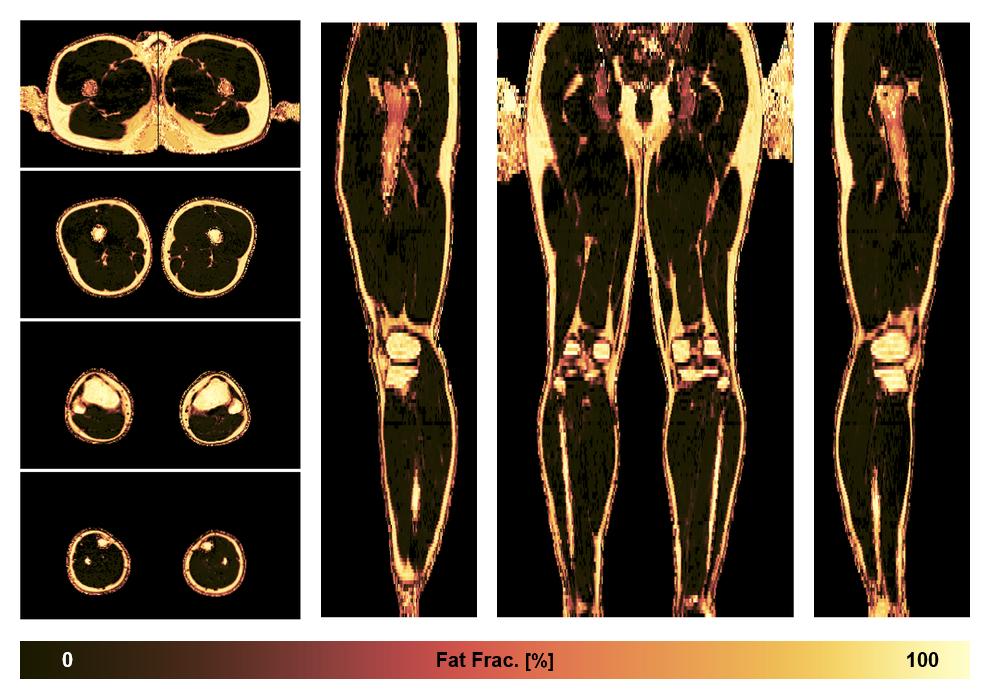

• Fat fraction

The fat fraction of the lower extremity obtained from the dixon reconstruction for muscle water fat quantification.